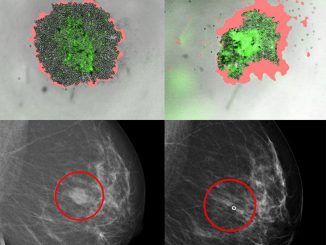

New method predicts the right treatment for breast cancer patients

Researchers at Karolinska Institutet have developed a method that should be able to predict whether a patient with breast cancer […]